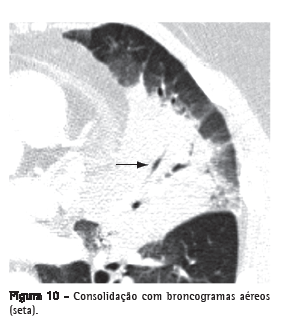

Broncograma aéreoTradução radiológica da identificação de brônquio(s) contendo ar, circundado(s) por parênquima pulmonar doente, onde o ar dos espaços aéreos foi substituído por um produto patológico qualquer, radiologicamente mais denso que o ar (por ex.: transudato, exsudato, sangue, produto de acúmulo ou células neoplásicas). Em geral, é a expressão utilizada quando se identifica uma imagem tubular gasosa (hipodensa), no interior de uma área de pulmão opacificado (Figuras 3 e 10). Essa imagem tubular deve ter o tamanho e a orientação usual de um brônquio ou de vários brônquios, presumivelmente representando um segmento da árvore brônquica.(22,23)

ConsolidaçãoRepresenta o preenchimento, com substituição do ar, dos espaços alveolares por um produto patológico qualquer, como, por exemplo, exsudato inflamatório (pneumonia), transudato (edema), sangue (hemorragia alveolar), lipoproteína (proteinose alveolar), gordura (pneumonia lipoídica), células (carcinoma bronquioloalveolar, linfoma, pneumonia em organização) ou conteúdo gástrico (pneumonia aspirativa).(32) Na TC, manifesta-se como um aumento da atenuação do parênquima pulmonar que impede a visualização dos vasos e dos contornos externos das paredes brônquicas. Broncogramas aéreos podem ser encontrados (Figuras 3 e 10). O valor de atenuação do parênquima consolidado, ao exame de TC sem contraste, raramente é útil no diagnóstico diferencial, exceto em algumas situações (por ex.: baixa atenuação na pneumonia lipoídica e alta atenuação na toxicidade por amiodarona).(33,34)